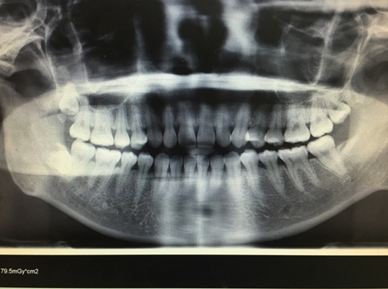

因为我已经拍过xray确认过我牙齿的健康情况了,所以就跳过了这一步,不过也可以附上之前在其他诊所拍的图,供大家欣赏。

大晚上看这种图可能不太好,但是也可以看出来我是明显的开咬合和过咬合。